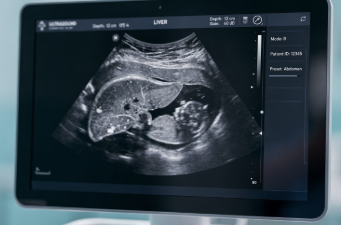

간수치는 보통 혈액검사에서 확인하는 간 효소 수치를 말합니다.

이 수치들은 간세포 안에 존재하는 효소입니다.

간세포가 손상되면 이 효소들이 혈액으로 빠져나오면서 수치가 상승합니다.

즉, 간수치 상승은 ‘간세포 손상이 발생했다’는 신호이지, 그 자체가 병명은 아닙니다.